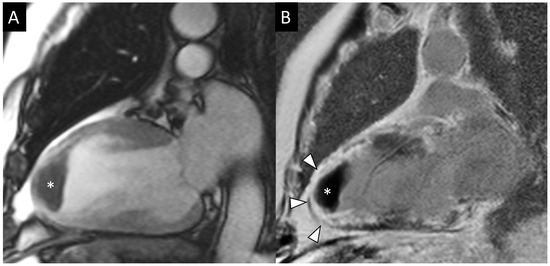

- Calvieri, C.; Masselli, G.; Monti, R.; Spreca, M.; Gualdi, G.F.; Fedele, F. Intramyocardial hemorrhage: An enigma for cardiac MRI? Biomed. Res. Int. 2015, 2015, 859073. [Google Scholar] [CrossRef]

- Galea, N.; Dacquino, G.M.; Ammendola, R.M.; Coco, S.; Agati, L.; De Luca, L.; Carbone, I.; Fedele, F.; Catalano, C.; Francone, M. Microvascular obstruction extent predicts major adverse cardiovascular events in patients with acute myocardial infarction and preserved ejection fraction. Eur. Radiol. 2019, 29, 2369–2377. [Google Scholar] [CrossRef] [PubMed]

- Abbas, A.; Matthews, G.H.; Brown, I.W.; Shambrook, J.S.; Peebles, C.R.; Harden, S.P. Cardiac MR assessment of microvascular obstruction. Br. J. Radiol. 2015, 88, 20140470. [Google Scholar] [CrossRef] [PubMed]

- Nijveldt, R.; Hofman, M.B.; Hirsch, A.; Beek, A.M.; Umans, V.A.; Algra, P.R.; Piek, J.J.; van Rossum, A.C. Assessment of microvascular obstruction and prediction of short-term remodeling after acute myocardial infarction: Cardiac MR imaging study. Radiology 2009, 250, 363–370. [Google Scholar] [CrossRef] [PubMed]